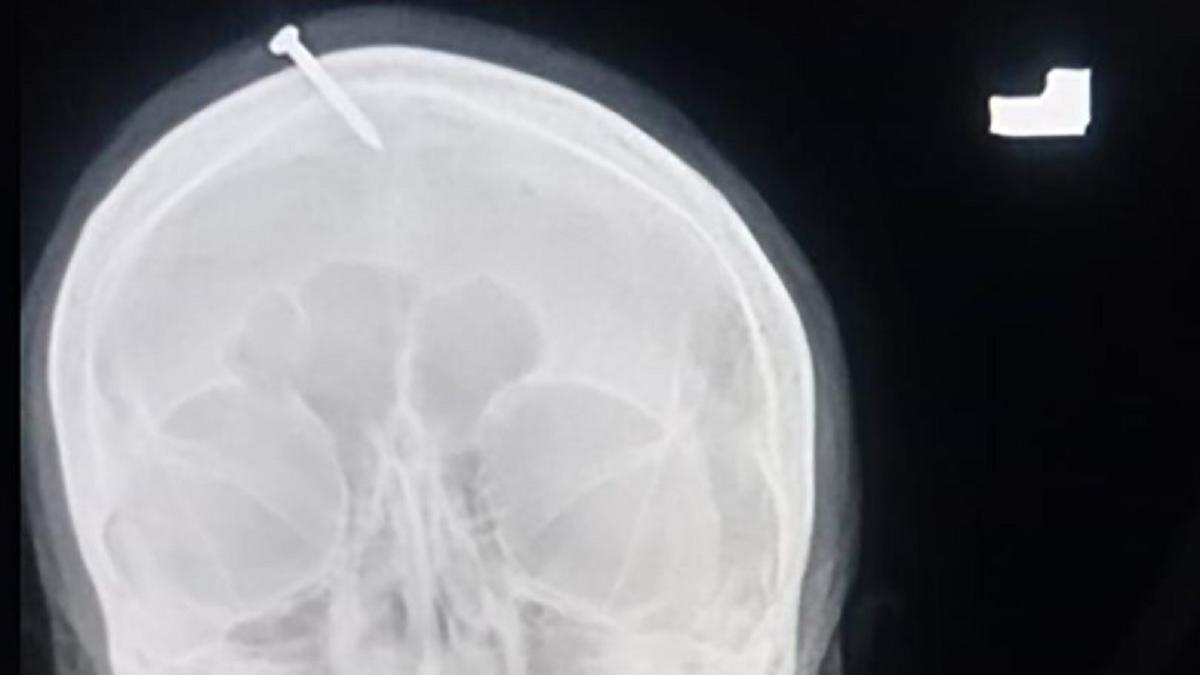

महिला के सिर का एक्‍स-रे

Pakistan Peshawar news: एक गर्भवती महिला (Pregnant woman) के सिर में एक फर्जी पीर ने ये कहकर कील ठोक दी कि गारंटी है कि जो बच्‍चा वह पैदा करेगी, वह लड़का ही होगा. ये मामला पाकिस्‍तान (Pakistan) का है. महिला के सिर में कील ठोकने के बाद उन्‍हें अस्‍पताल ले जाया गया. उनके सिर में करीब दो इंच तक ये कील सनकी पीर ने ठोक दी.

ये घटना पाकिस्‍तान  के पेशावर शहर की है. जहां महिला लेडी रीडिंग हॉस्पिटल इलाज के लिए पहुंची थी. उसके सिर के अंदर तक दो इंच तक ये कील घुसी हुई थी. महिला ने शुरुआत में बताया कि उसने ये सब एक पीर के कहने पर किया, लेकिन बाद में वह बोली कि ऐसा पीर ने ही किया है .

दरअसल, ये महिला पहले से ही तीन बेटियों की मां है. जियो न्‍यूज के मुताबिक, इस फर्जी पीर ने कहा कि सिर में कील लगानी होगी, इससे बेटा ही होगा. इसके बाद महिला के सिर में कील ठोक दी गई थी. फिर उसे घायल अवस्‍था में अस्‍पताल लाया गया. जहां उसके सिर की सर्जरी की गई. न्‍यूरो सर्जन डॉ. हैदर ने बताया कि महिला के सिर में गंभीर चोट थी. उसके सिर में काफी खून बह रहा था. महिला ने बाद में पुष्टि की उनको बेटे की चाहत थी, ऐसे में पीर के कहने पर उन्‍होंने ऐसा कर दिया. जियो न्‍यूज की रिपोर्ट के मुताबिक महिला पढ़ी- लिखी हुई नहीं थी. वहीं पाकिस्‍तानी मीडिया के मुताबिक, इस मामले की जांच की जा रही है.